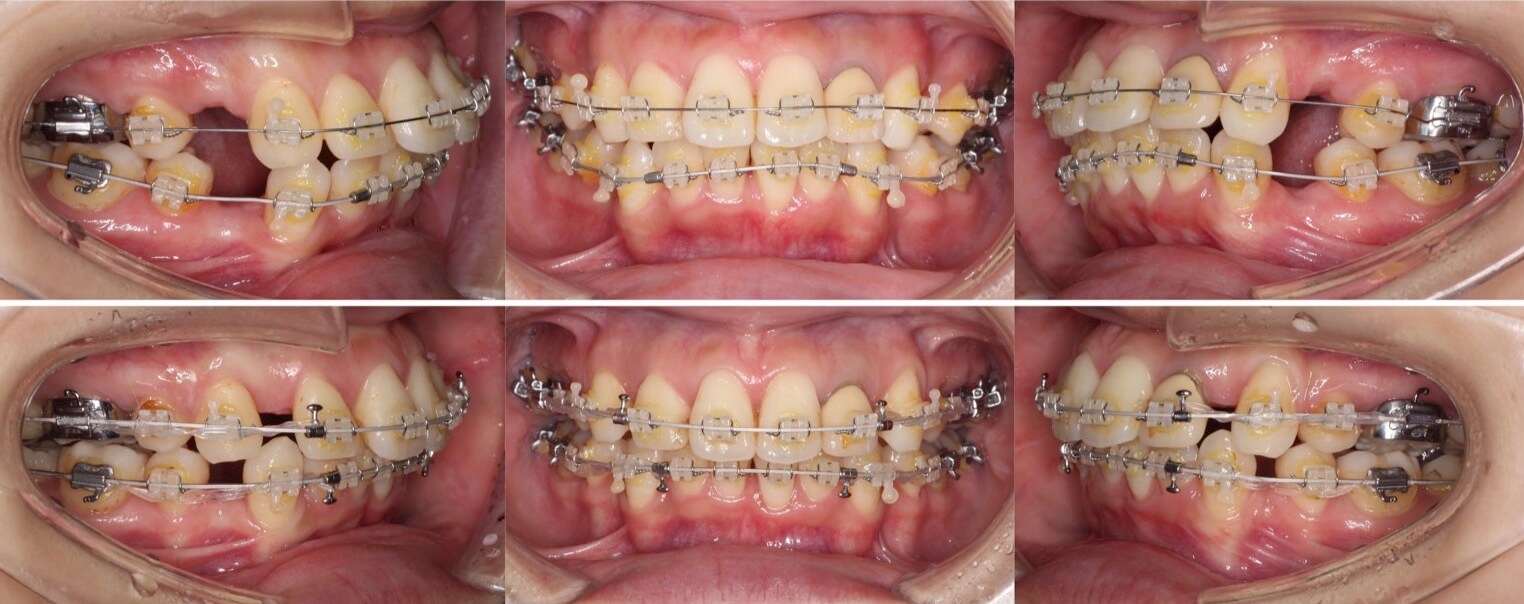

「男性は顔が引き締まる」

高校生男性・唇側矯正装置・下あご後退型

当初は、抜歯矯正治療にするかしないかで、治療方針に迷ったケースですが、最終的には患者さんの希望に沿って抜歯矯正治療にしました。歯の動きがゆっくりであったため、治療期間が3年を超えてしまいました。

<症例概要> 難易度:★★★★☆

主訴:口元の突出・前歯のガタツキ

年齢・性別:高校生男性

住まい:千葉県八千代市市

症状:下顎後退・叢生

治療方針:抜歯空隙の閉鎖(最大固定)

治療装置:唇側矯正装置

固定:歯科矯正用アンカースクリュー(頬側x2)

抜歯:上下第一小臼歯(計4本)

治療期間:3年4か月

リテーナー:上下プレートタイプ+フィックスタイプ

治療費用:968,000(税込)

代表的副作用:痛み・治療後の後戻り・歯根吸収・歯髄壊死・歯肉退縮